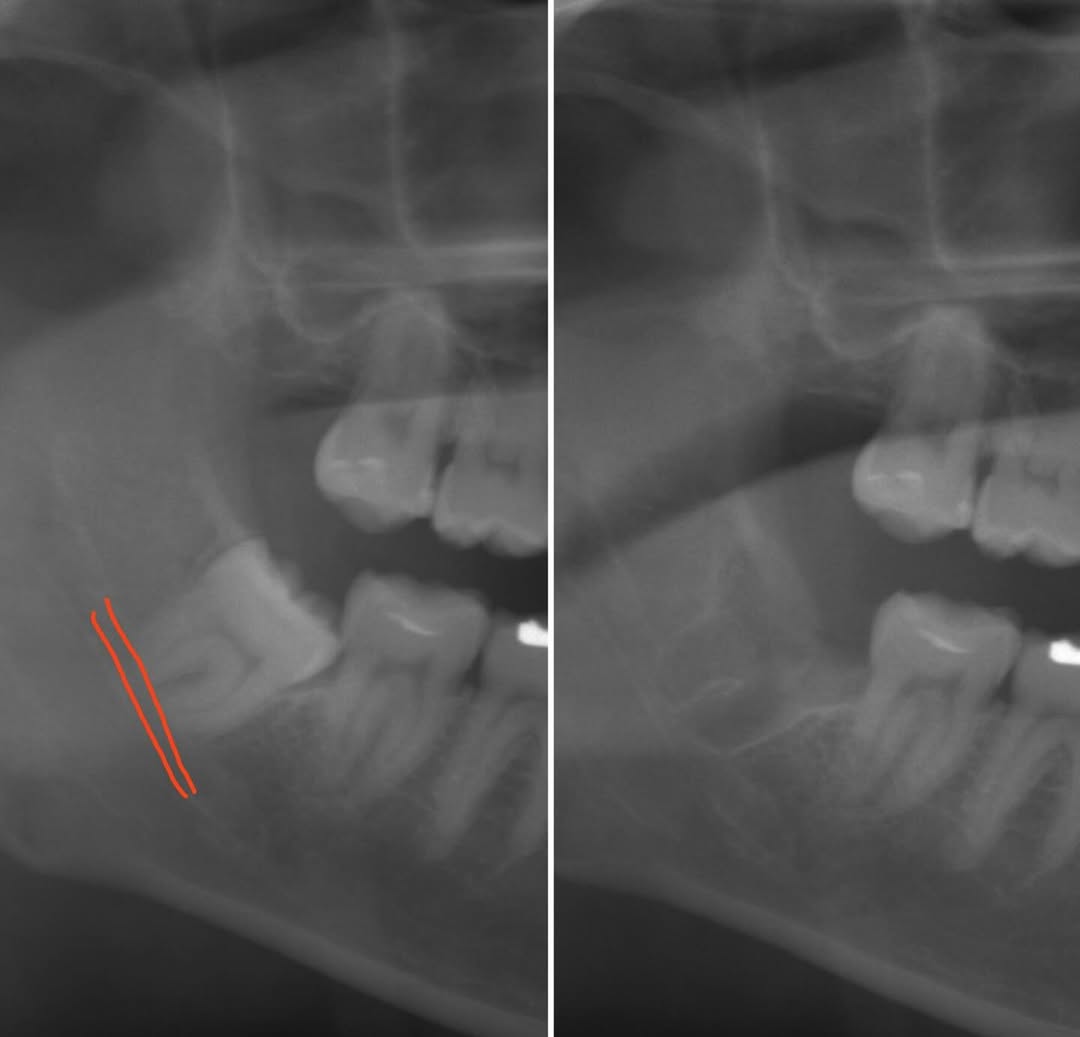

IMPLANT 埋入実績累計2万本以上 専門医を中心とした

チームが行う インプラント治療-

新宿の歯医者「新宿KU歯科」が属する「KU歯科クリニック」グループでは、これまでに累計2万本以上のインプラント手術を行ってまいりました。豊富な治療実績を持つインプラント専門医を中心としたチームを結成し、さまざまな分野の専門家の英知を集結させ、顎の骨が少ない方や他院から治療を断られた難症例の方の治療にも対応します。